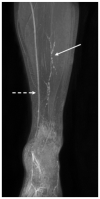

Background: Clinical examination and lymphoscintigraphy are the current standard for investigating lymphatic function. Magnetic resonance imaging (MRI) facilitates three-dimensional (3D), nonionizing imaging of the lymphatic vasculature, including functional assessments of lymphatic flow, and may improve diagnosis and treatment planning in disease states such as lymphedema.

Results: From 612 identified articles, 43 articles were included and their protocols and results summarized. Field strength was 1.5 or 3.0 T in all studies, with 25/43 (58%) employing 3.0 T imaging. Most commonly, imaging of the peripheries, upper and lower limbs including the pelvis (32/43, 74%), and the trunk (10/43, 23%) is performed, including two studies covering both regions. Imaging protocols were heterogenous; however, T2 -weighted and contrast-enhanced T1 -weighted images are routinely acquired and demonstrate the lymphatic vasculature. Edema, vessel, quantity and morphology, and contrast uptake characteristics are commonly reported indicators of lymphatic dysfunction.